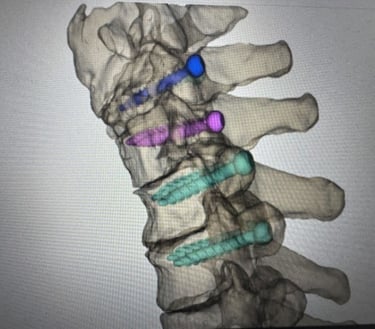

Reached out to a local surgeon for past segmentation data; utilized Materialise 3-matic to fabricate a surgical guide for a past posterior cervical surgery.

The guide was created specifically for C6, and pedicle screw placement is used, with documentation advising the use of an inserter (torque direction).

Backtesting on this past case and a few other similar ones has allowed me to understand how to communicate with surgeons as well as incorporate feedback; in this case, as the meshing shows, C6 was an essential part of this case because it is the endpoint of fixation, along with C3 in blue. Without proper placement when drilling, post-op complications can occur just months after surgery, where the spine can become more out of spec, and more external hardware can be required, increasing cost and pain.